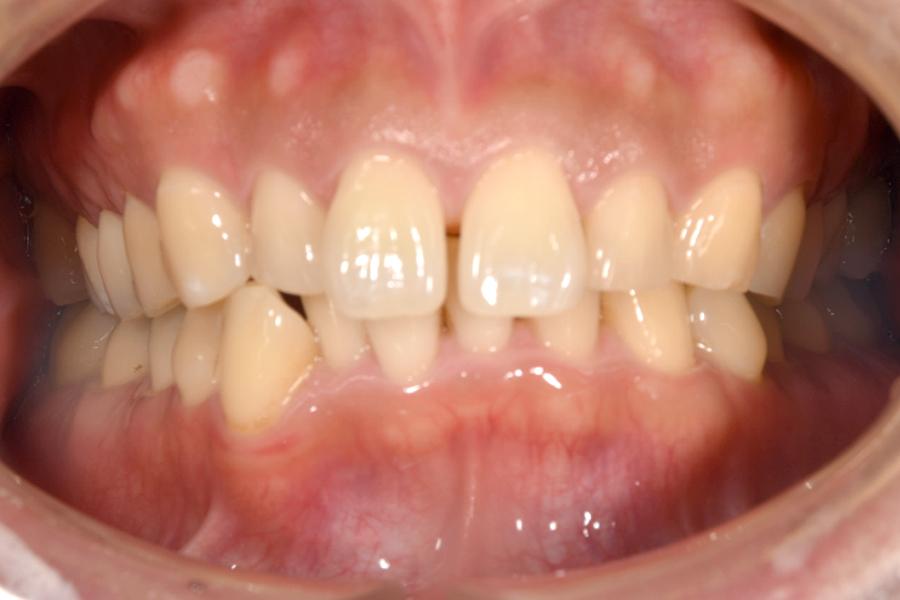

| 主訴 | 歯並びを治したい |

|---|---|

| 治療期間 | 5か月 |

| 治療費 | 部分マウスピース矯正(モニターキャンペーン)と ホワイトニングセット 422,596円(税込) |

| 治療内容 | 目立ちにくいマウスピース矯正 (非抜歯矯正) 歯と歯の間に隙間をつくることにより、歯列弓を広げながら治療を行いました。 また矯正用マウスピースをトレー代わりにし、ジェルを入れてホームホワイトニングを同時に行っております。 |

| 治療のリスク | ・後戻りする可能性があるのでリテーナーを最低でも矯正期間以上はつける必要があります。 ・ホワイトニング後、一時的に痛みが出る場合があります。 |